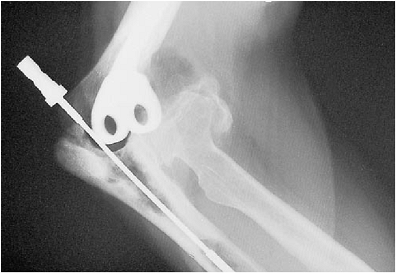

with a flexible reamer. Special 4.5- to 7-mm cannulated flexible

reamers are available for this purpose (Fig. 19-11).

If the canal has undergone extensive thinning or if there is concern

about the likelihood of penetration of the canal, a radiograph taken

with the instrument down the medullary canal may be obtained to ensure

containment within the canal. Penetration allows extravasation of the

cement, causes loss of effective compression, increases the possibility

of stress fracture, and may cause mechanical or thermal damage to the

nerve (Fig. 19-12). If moderate osseous